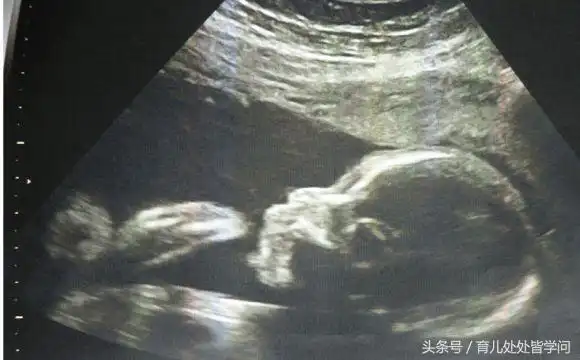

b超单子上有男女暗示吗?教你如何看胎儿性别